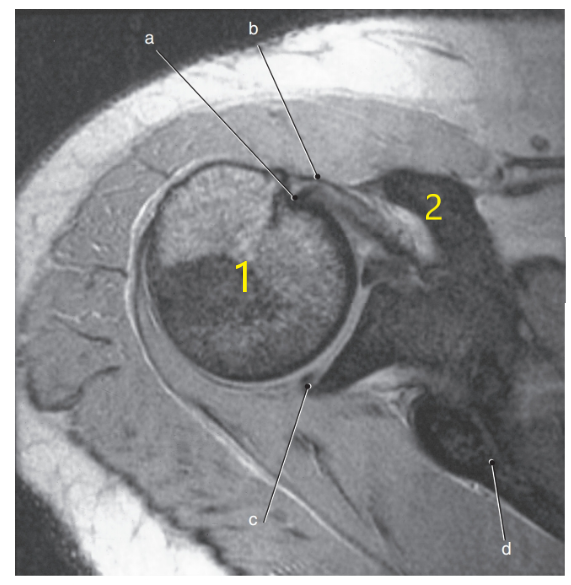

What anatomy is # 1 ?

Humeral head

What anatomy is # 2 ?

Scapula

What is letter c ?

Superior glenoid labrum

Glenohumeral joint

Posterior glenoid labrum

What is letter a?

Biceps brachii tendon

Subscapularis tendon